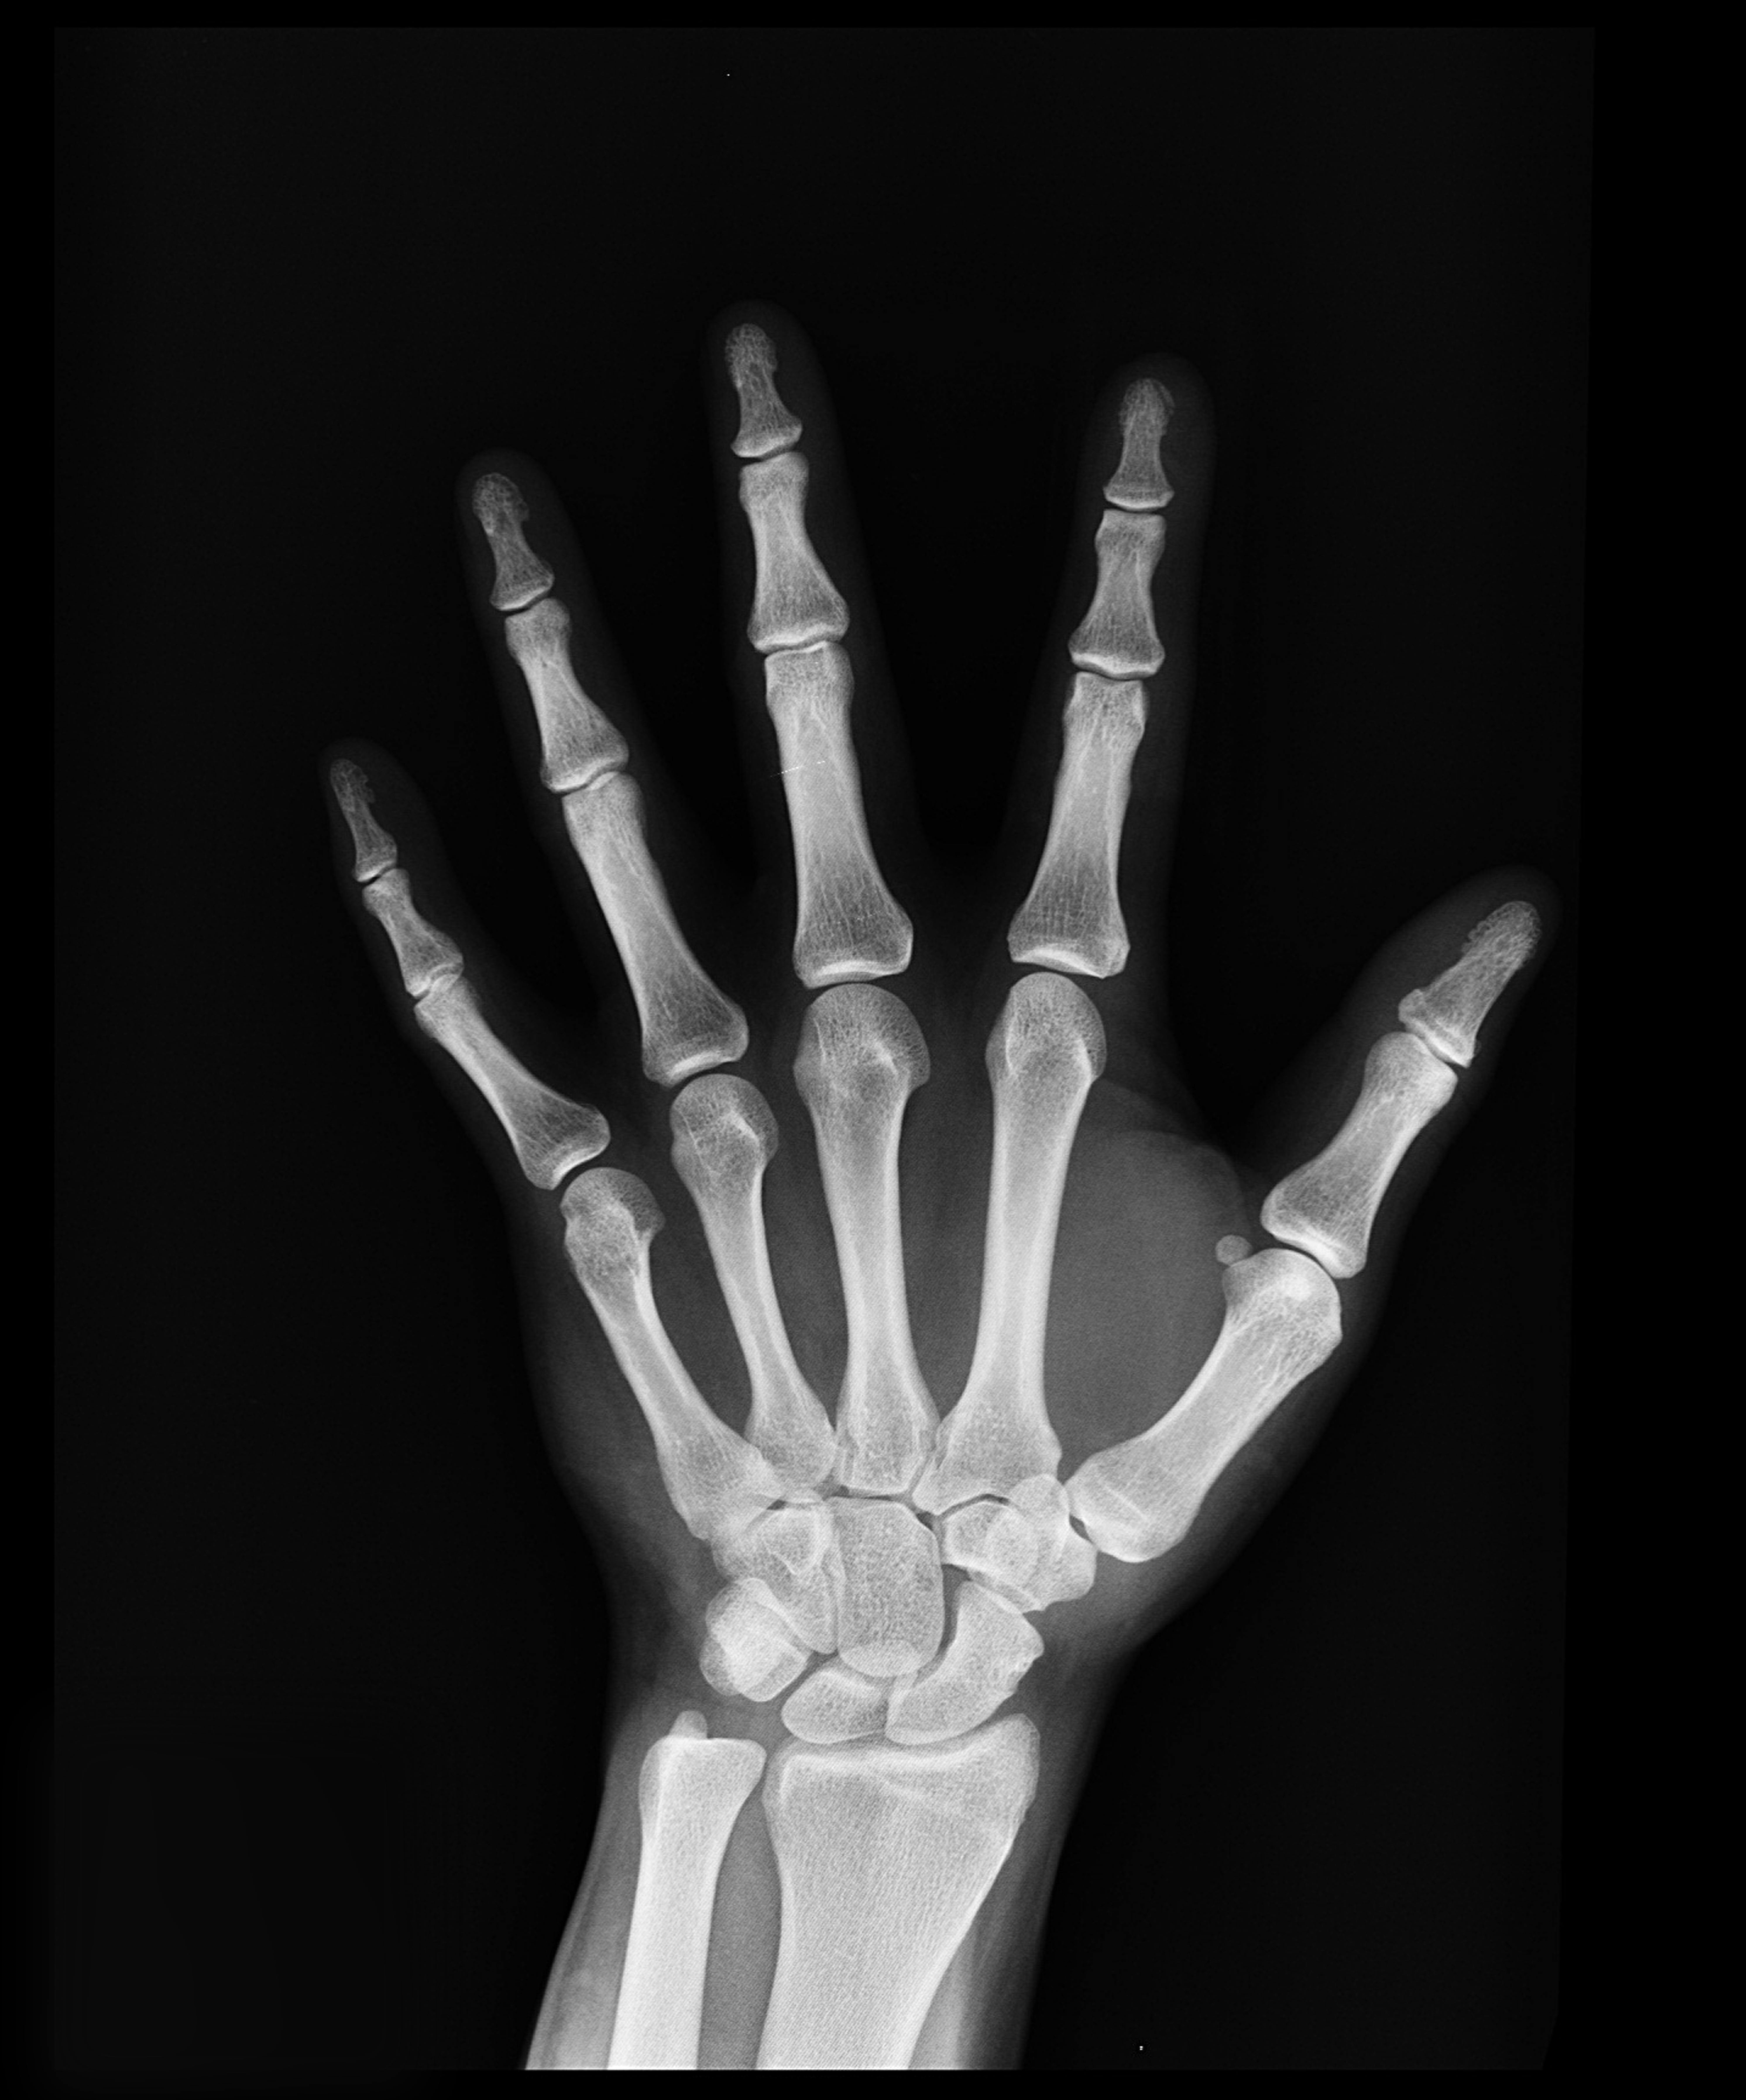

Obrazowanie rentgenowskie ręki umożliwia szczegółową ocenę struktur kostnych w obrębie dłoni, nadgarstka oraz części przedramienia. Na zdjęciu RTG widoczne są przede wszystkim kości śródręcza, paliczków, a także fragmenty kości promieniowej i łokciowej. Dzięki temu badanie pozwala na precyzyjne uwidocznienie zarówno drobnych, jak i bardziej rozległych zmian w układzie kostnym, co jest niezwykle istotne w diagnostyce urazów oraz przewlekłych schorzeń.

Za pomocą prześwietlenia można wykryć różnorodne nieprawidłowości, takie jak złamania, pęknięcia, zmiany zwyrodnieniowe czy zmiany czynnościowe w obrębie stawów. RTG ręki pozwala również na rozpoznanie zmiażdżeń kości, a także ocenić ewentualne zerwania więzadeł lub inne uszkodzenia tkanek okołostawowych. Badanie to jest nieocenione w różnicowaniu przyczyn dolegliwości bólowych oraz ograniczenia ruchomości ręki, umożliwiając szybkie podjęcie decyzji o dalszym postępowaniu diagnostycznym lub terapeutycznym. W przypadku przewlekłych problemów, takich jak reumatoidalne zapalenie stawów, zdjęcie rentgenowskie pozwala monitorować postęp choroby i skuteczność leczenia. Warto również pamiętać, że RTG może być pomocne w ocenie zmian pourazowych u osób aktywnych fizycznie czy sportowców, a także w diagnostyce powikłań po zabiegach chirurgicznych.